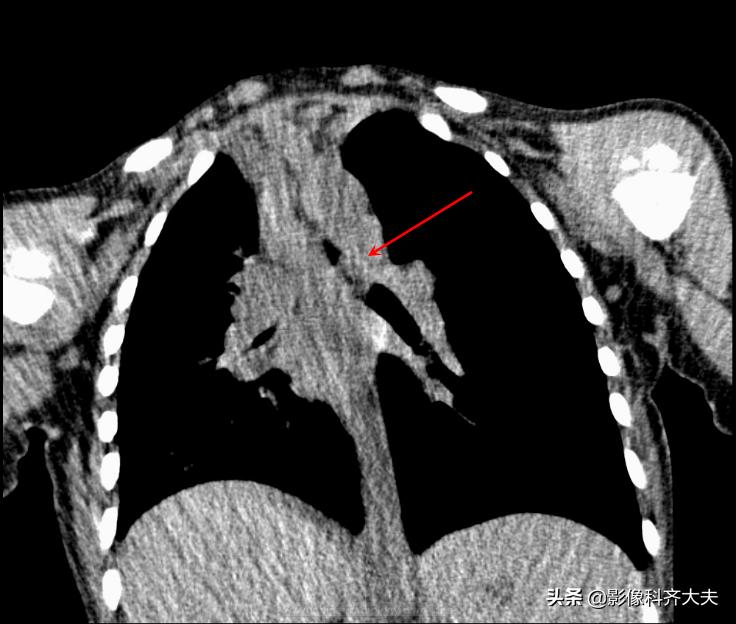

病例6、病史:女,两岁,吃花生时喝水引起呛咳。

轴位显示左侧支气管疑似异物,红色箭头。

冠状位重建清晰显示左侧支气管异物,红色箭头所示。